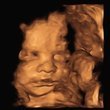

Önümüzdeki hafta detaylı ultrasonum var. Oldukça heyecanlıyım hem bebeğimi daha detaylı görüp ondan haberler alacağım için hem de 3D ultrason görüntüsünü çok merak ettiğim için… Tek dileğim güzel haberler duymak…